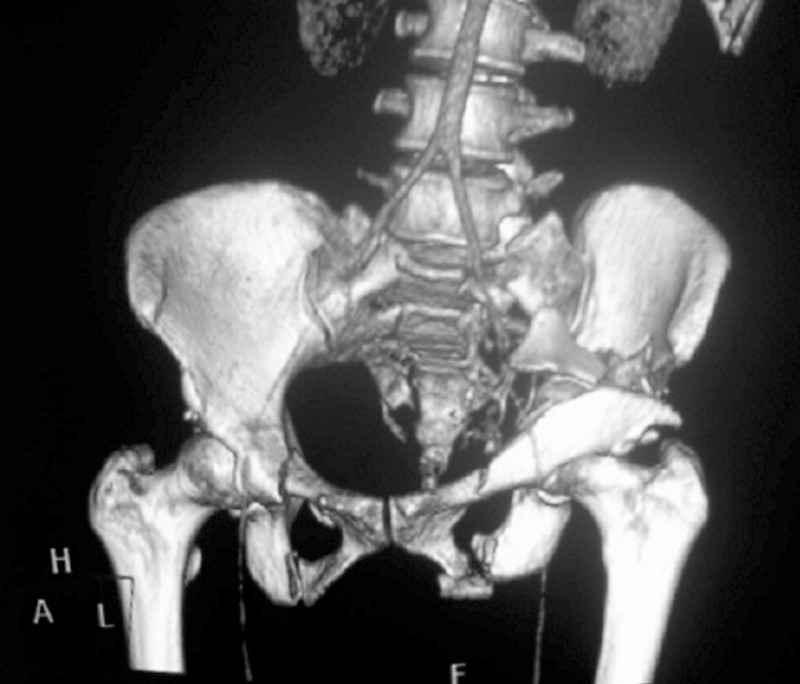

General condition is fine except for an intractable pelvic pain, no associated injuries (only ankle fracture), no sciatic nerve injury.

The soft tissues are also in mild condition, buttock hematoma and probably a Morel-Lavalle. I send some more CT images. There are some conminution in the posterior column (I don’t have images now). The patient is scheduled for surgery next Monday. The plan is percutaneous sacral fixation and then ilioinguinal approach .